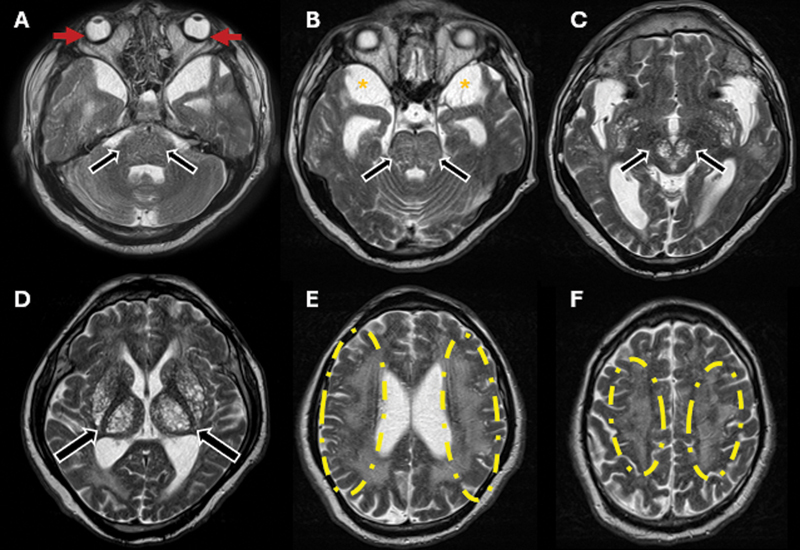

The hidden burden of lysosomal dysfunction: visual decline and microphthalmia in Hunter syndrome.